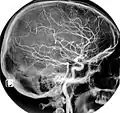

The common carotid artery and its main branches

In anatomy, the left and right common carotid arteries (carotids) (English: /kəˈrɒtɪd/[1][2]) are arteries that supply the head and neck with oxygenated blood; they divide in the neck to form the external and internal carotid arteries.[3][4]

The common carotid arteries are present on the left and right sides of the body. These arteries originate from different arteries but follow symmetrical courses. The right common carotid originates in the neck from the brachiocephalic trunk; the left from the aortic arch in the thorax. These split into the external and internal carotid arteries at the upper border of the thyroid cartilage, at around the level of the fourth cervical vertebra.

At approximately the level of the fourth cervical vertebra, the common carotid artery splits ("bifurcates" in literature) into an internal carotid artery (ICA) and an external carotid artery (ECA). While both branches travel upward, the internal carotid takes a deeper (more internal) path, eventually travelling up into the skull to supply the brain. The external carotid artery travels more closely to the surface, and sends off numerous branches that supply the neck and face.